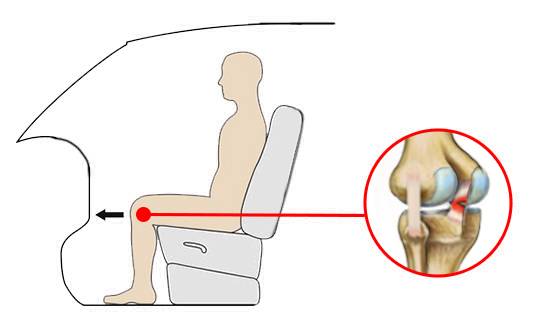

Uraz najczęściej występuje w wyniku wymuszonego tylnego przemieszczenia piszczeli. Do rozerwania PCL jest konieczna duża siła, dlatego bardzo często przyczyną urazu są wypadki samochodowe, gdzie dochodzi do uderzenia kolanem o deskę rozdzielczą.

Uraz najczęściej występuje w wyniku wymuszonego tylnego przemieszczenia piszczeli. Do rozerwania PCL jest konieczna duża siła, dlatego bardzo często przyczyną urazu są wypadki samochodowe, gdzie dochodzi do uderzenia kolanem o deskę rozdzielczą.

Orteza kolana RAPTOR/2RA stabilizuje staw w płaszczyźnie strzałkowej i czołowej. Orteza RAPTOR/2RA posiada 4-punktowy system podparcia, który doskonale stabilizuje i odciąża staw kolanowy. W przypadku uszkodzonego więzadła krzyżowego tylnego (PCL), kość piszczelowa ma tendencję do nadmiernego przemieszczania się w kierunku tylnym względem kości udowej. Konstrukcja przednio-tylna ortezy pozwala na zabezpieczenie piszczeli i ustawienie jej w osi stawu kolanowego.

W przypadku uszkodzonego więzadła krzyżowego tylnego (PCL), kość piszczelowa ma tendencję do nadmiernego przemieszczania się w kierunku tylnym względem kości udowej. Konstrukcja przednio-tylna ortezy pozwala na zabezpieczenie piszczeli i ustawienie jej w osi stawu kolanowego.